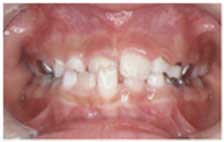

25. 交叉咬合:   一部の歯が前後逆のかみ合わせ

一部の歯が前後逆のかみ合わせを、交叉咬合と呼びます。

交叉咬合になっている部分の歯は、反対咬合の場合と同じように、ぐらぐらしたり、歯肉が下がったりする事があります。

また、左右非対称に交叉咬合がある場合は、顎の成長方向も左右非対称になり、顎が曲がって成長してしまうこともあります。